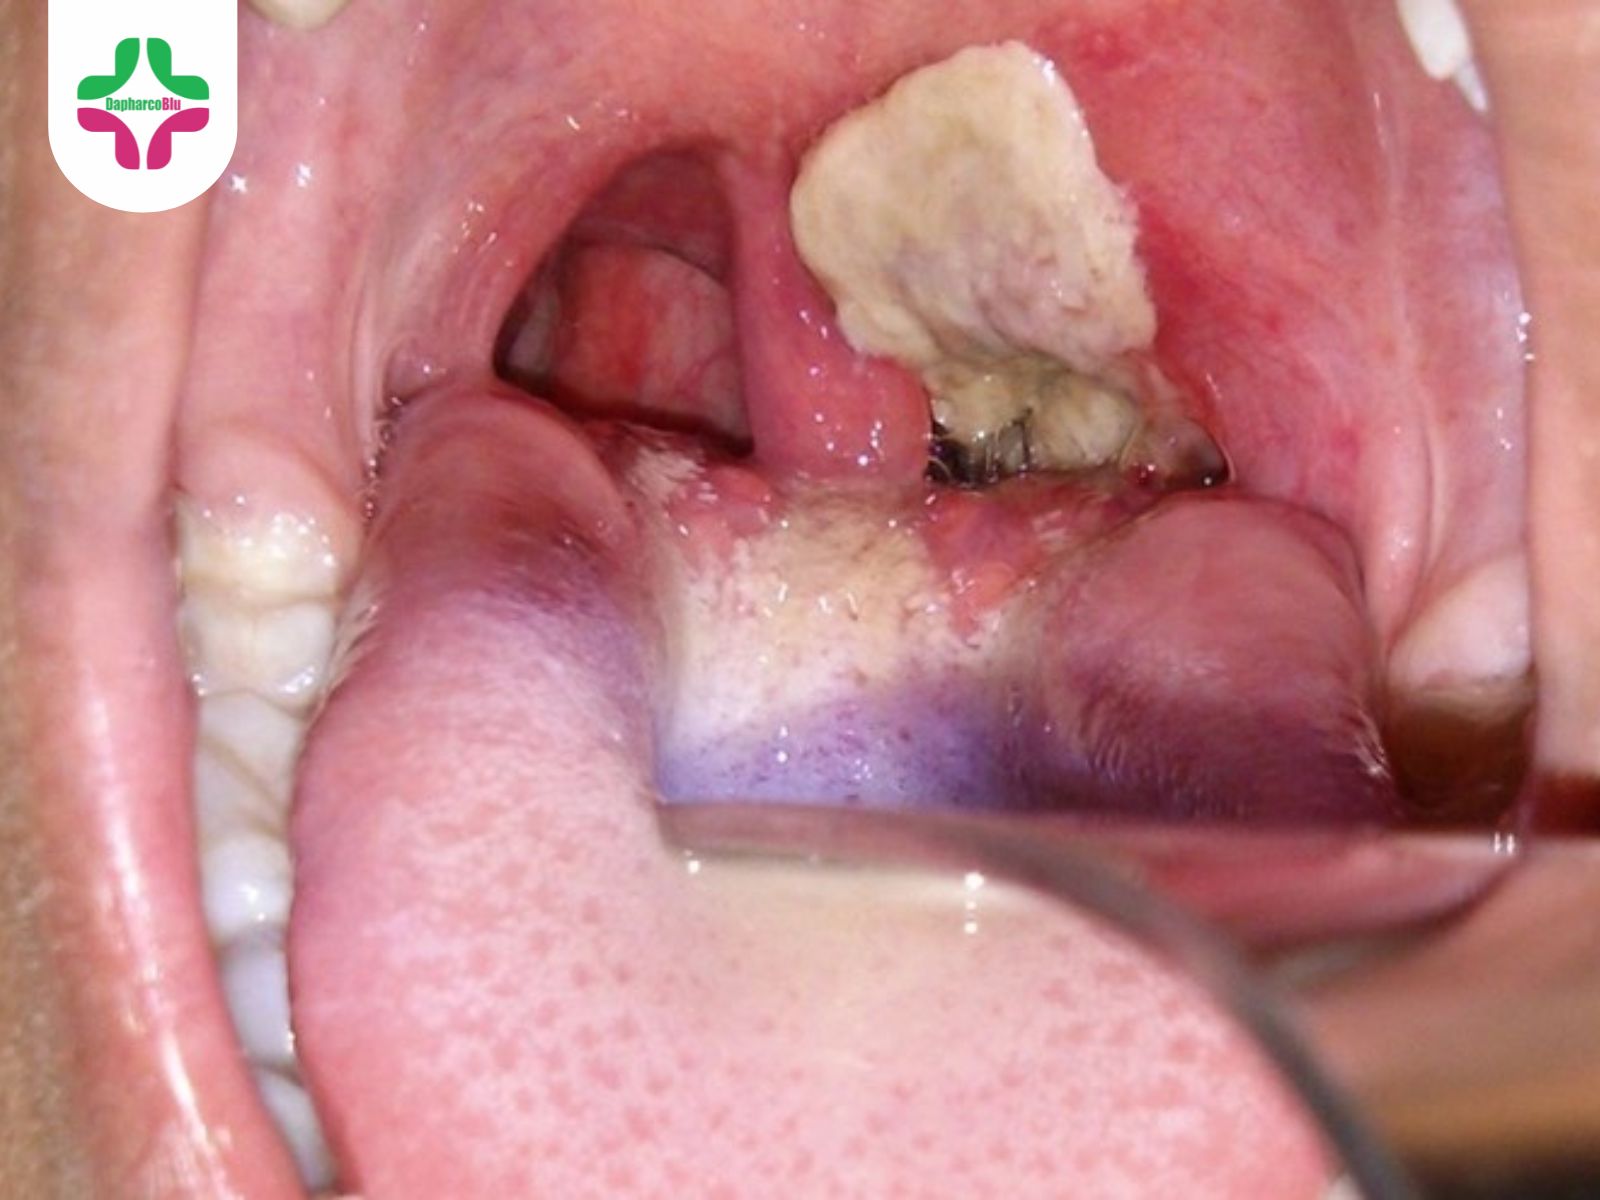

Bệnh bạch hầu có các triệu chứng như viêm họng, viêm mũi, viêm thanh quản, cổ họng đỏ, nuốt đau, da xanh xao, mệt mỏi, nổi hạch dưới hàm gây sưng tấy vùng cổ, và khi khám thấy có giả mạc. Thể bệnh bạch hầu thanh quản đặc biệt nặng, thường gặp ở trẻ em, với các triệu chứng như nhiễm độc thần kinh, tê liệt thần kinh sọ não, thần kinh cảm giác, thần kinh vận động ngoại biên, và có thể viêm cơ tim. Nếu không được điều trị kịp thời, bệnh có thể gây tử vong trong vòng 6-10 ngày. Bệnh có thể được chữa trị bằng huyết thanh.